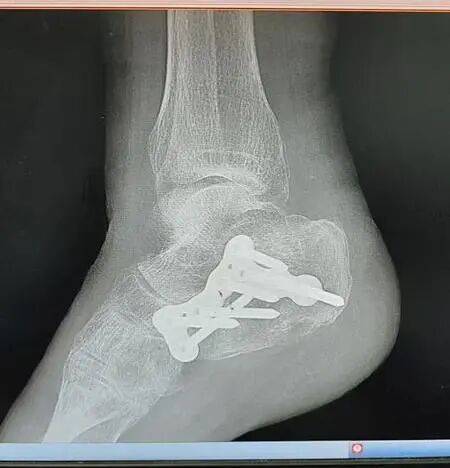

眼见老伴失去意识,孙老伯一时乱了方寸,连忙上前搀扶、连声呼唤,一旁的热心路人见状,主动帮忙拨打了120急救电话。大约十分钟后,救护车抵达现场,将高阿婆送往就近的第十人民医院救治。经CT检查诊断,高阿婆右侧踝关节、右侧肩关节等共三处骨折,伤情较为严重,需立即接受治疗。“当时一门心思都在老伴身上,根本没想起来报警,等反应过来,涉事的845路公交车早就开走了。”

诊断结果